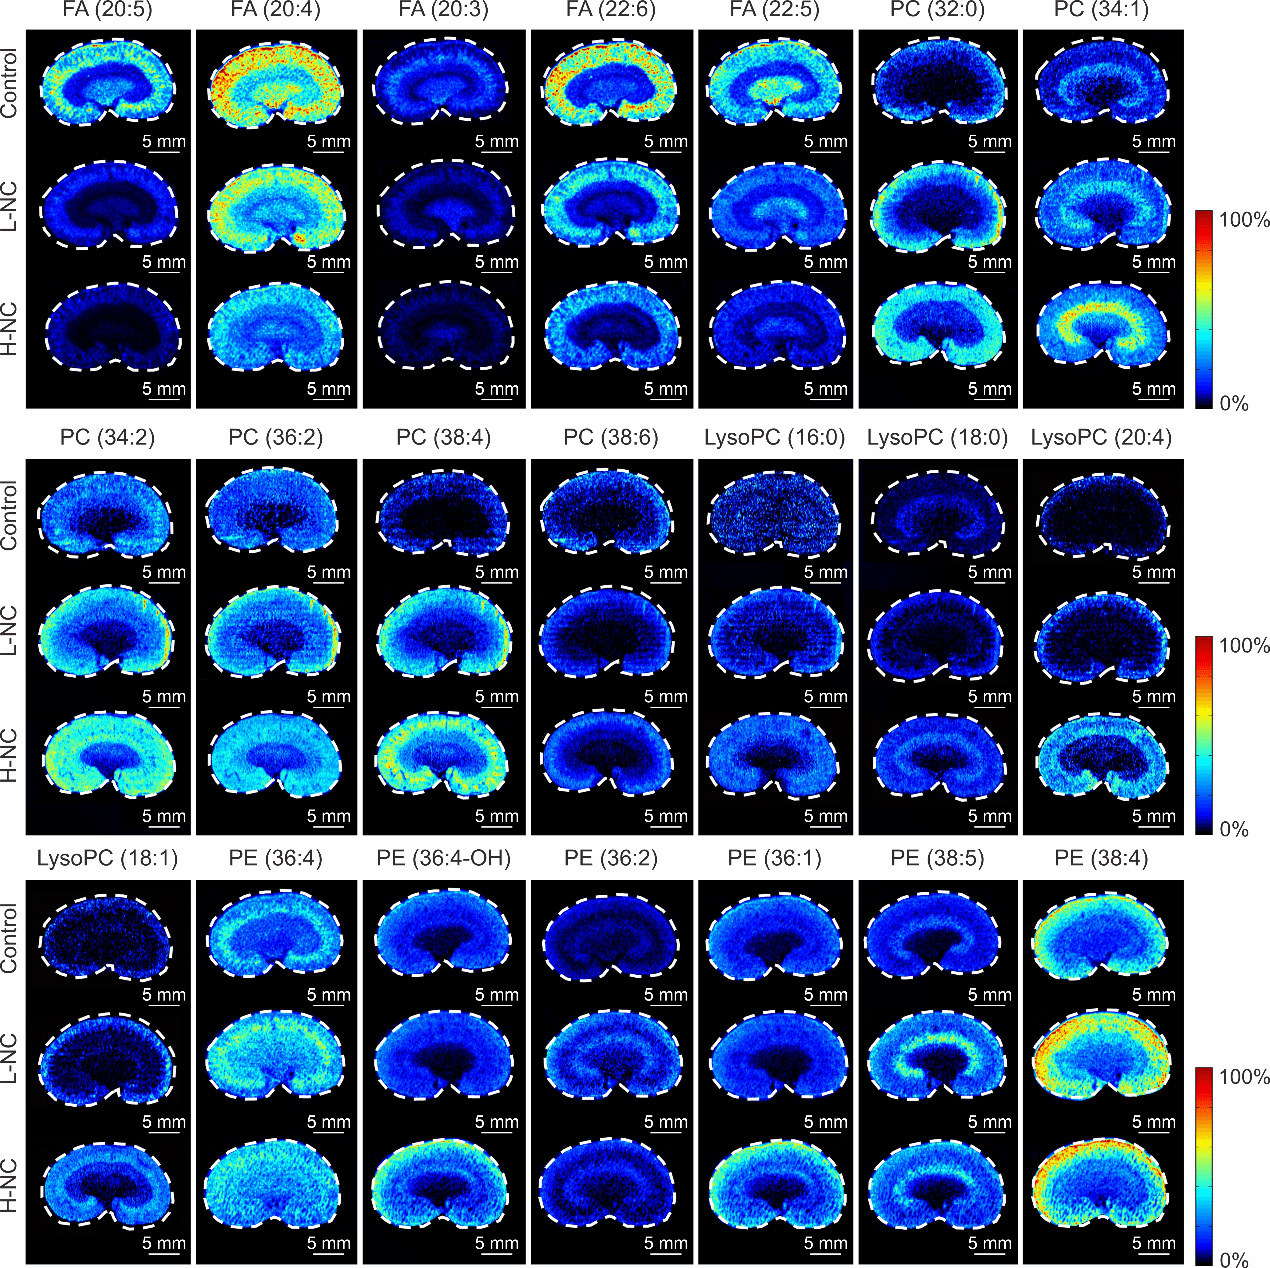

图4 肾脏组织中参与脂质代谢途径的差异代谢物空间分布图像。

Control:空白对照组,L-NC:低剂量NC(2 mg/kg)给药组,H-NC:高剂量NC(6 mg/kg)给药组。